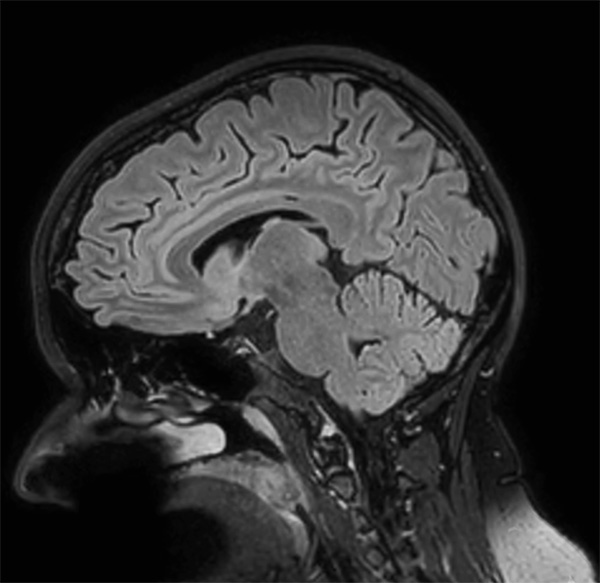

Comprehensive Brain imaging at 3.0T

• Clinical Application